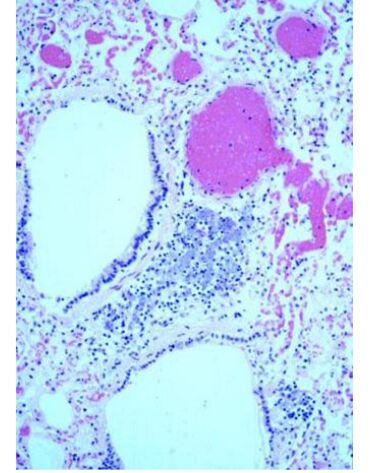

(C)碳素沈著病  (anthracosis):此是肺塵埃沉著病  (pneumoconiosis) 的一種。吸入含碳的塵埃到肺,稱為碳素沈著病(anthracosis) 。都市的狗常見此病。早期在臺北市區長大的狗都可見此病。肉眼下,肺臟可變成灰色。鏡下可見黑色的碳化物沈著於小支氣管的周圍,大多在巨噬細胞內。另外,於支氣管的淋巴腺,也可見碳的沈積。

這是因吸入的碳化物經淋巴管排出到淋巴腺。經吸入並附著在上呼吸道的塵埃,部分可經呼吸道上皮的黏液纖毛系統(mucocilliary) 排出。

圖 6-1. 狗肺切片,於支氣管周圍有塵埃的沈著,稱肺塵埃沉著病(pneumoconiosis)  ,這是一種外來性的色素沈著。